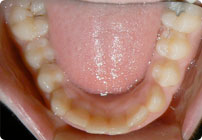

Caso: 11 años

Adolescente: Clase II

Mordida Cruzada Posterior

Sin extracción

Sin uso de expansores

6 alambres superiores

5 alambres inferiores

Sin uso de elásticos

Retenedores: Interior Fijo de TMA y Hawley en superior

Tiempo de tratamiento: 14 Visitas